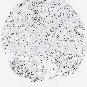

PANCREATIC CANCER - Protein expressioni

A mouse-over function shows sample information and annotation data. Click on an image to view it in a full screen mode. Samples can be filtered based on level of antibody staining by selecting one or several of the following categories: high, medium, low and not detected. The assay and annotation is described here.

Note that samples used for immunohistochemistry by the Human Protein Atlas do not correspond to samples in the TCGA dataset.

Antibody stainingi

Antibody staining in the annotated cell types in the current human tissue is reported as not detected, low, medium, or high, based on conventional immunohistochemistry profiling in selected tissues. This score is based on the combination of the staining intensity and fraction of stained cells.

Each image is clickable and will lead to virtual microscopy that enables deeper exploration of all samples and also displays staining intensity scores, fraction scores and subcellular localization as well as patient and tissue information for each sample.

Antibody HPA003506

Antibody CAB005873

Staining

High

Medium

Low

Not detected

Intensity

Strong

Moderate

Weak

Negative

Quantity

>75%

75%-25%

<25%

None

Location

Nuclear

Cytoplasmic/membranous

Cytoplasmic/membranous,nuclear

Adenocarcinoma, NOS

Adenocarcinoma, metastatic, NOS